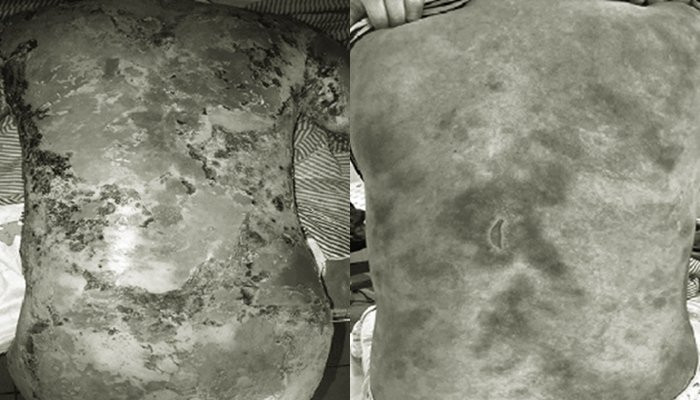

Bệnh nhân trước và sau khi được điều trj. (Ảnh: BVCC)

Sau 2 tháng điều trị tích cực, tổn thương da của bệnh nhân dần hồi phục, tình trạng rối loạn nước, điện giải, bội nhiễm được đẩy lùi.